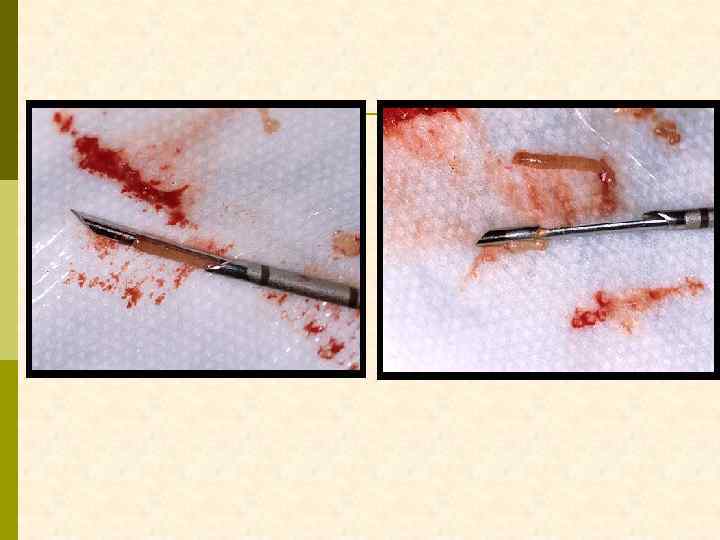

Кусочек, который изымается из почечной ткани при биопсии, соответствует длине и диаметру ложа пункционной иглы